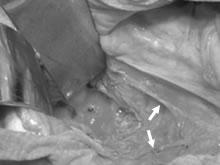

術中写真 1

術中写真 2

直腸切除後に肛門とS状結腸との吻合を行いました。